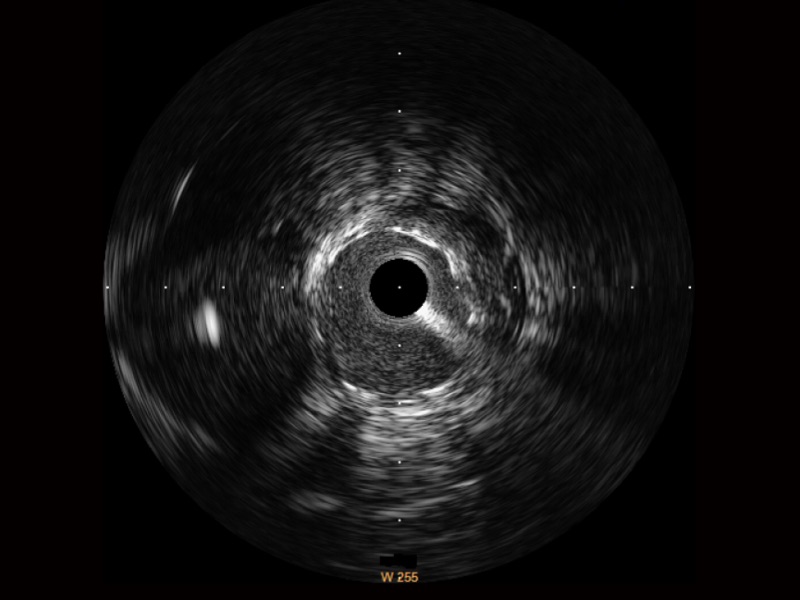

milan米兰宽频IVUS图像

传统IVUS图像

对比传统IVUS导管成像,milan米兰宽频IVUS图像的近场支架梁显影更细腻,远场中膜外血管仍清晰可辨,兼顾远中近,兼顾分辨力与穿透深度